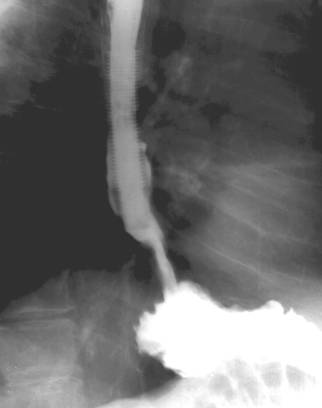

Figure 3. Malignant esophageal stenosis bridged with an endoscopically positioned plastic reinforced stent (Z-stent® - Wilson-Cook)